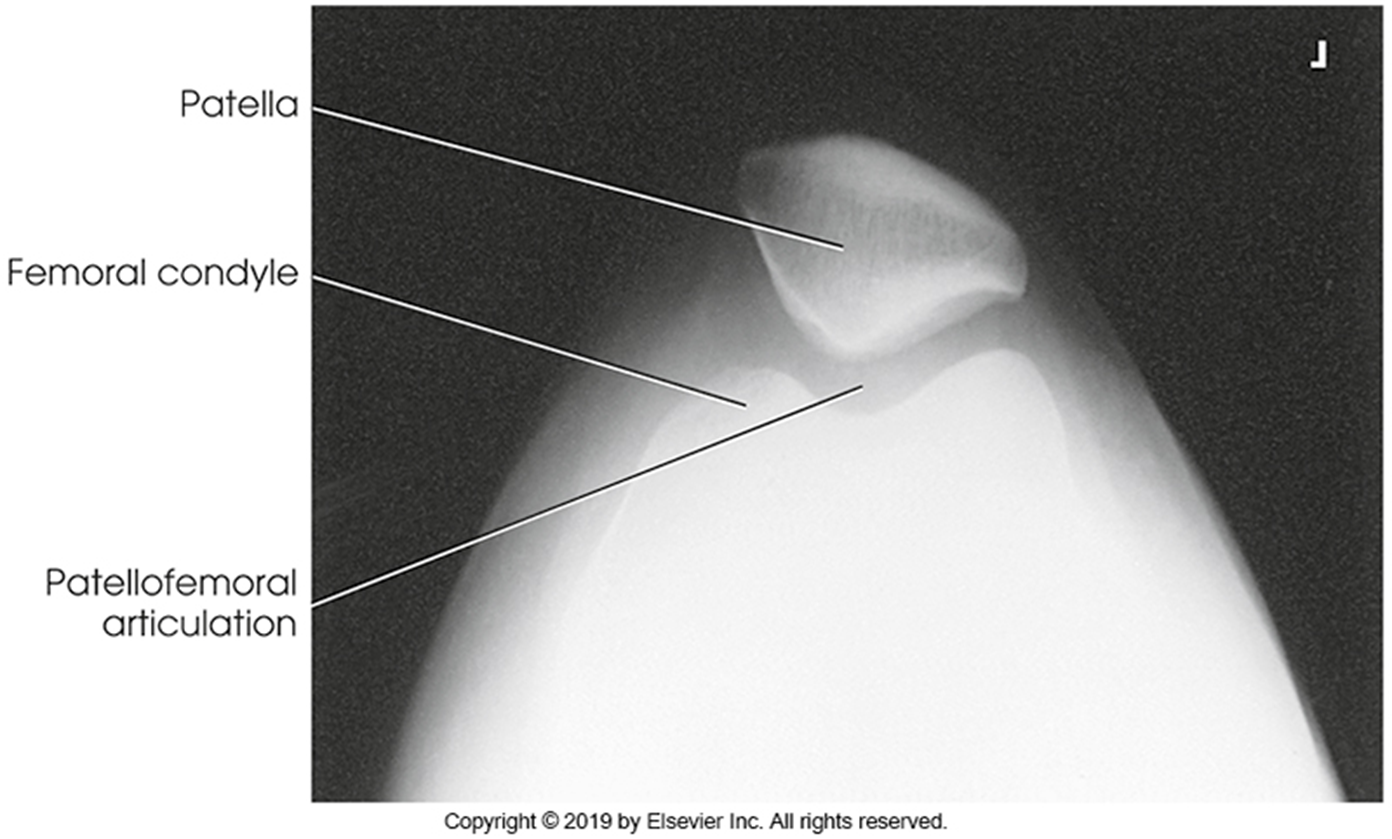

Trauma and Non-Trauma Lateral Knee (Mediolateral)

•Evidence of proper collimation and the presence of a side marker placed clear of the anatomy of interest

•Knee flexed 20 to 30 degrees in true lateral position as demonstrated by femoral condyles superimposed (locate the more magnified medial condyle)

•Anterior surface of medial condyle closer to patella results from over-rotation toward the image receptor (IR).

•Anterior surface of medial condyle farther from patella results from under- rotation away from the image receptor (IR).

•Inferior surface of medial condyle caudal to lateral condyle results from insufficient cephalad central ray (CR) angle.

•Inferior surface of lateral condyle caudal to medial condyle results from too far cephalad CR angle.

•Fibular head and tibia slightly superimposed (over rotation causes less superimposition, and under rotation causes more superimposition)

•Patella in a lateral profile

•Open patellofemoral joint space

•Open joint space between femoral condyles and tibia

•Bony trabecular detail and surrounding soft tissues